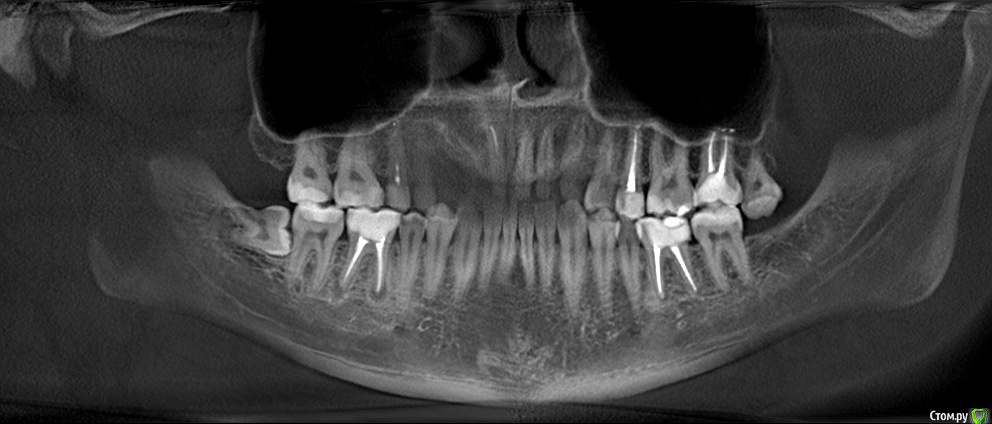

Добрый день! На протяжении нескольких лет обращался на профилактические осмоты - всегда говорили что Ок.

кто говорил, что 8ку удалять. А сходил к хирургу - сказал что все уже вырасло и раз не беспокоит - можно не трогать. Показаний нет.

В сейчас, опять сделали снимок и говорят, что на соседнем зубе кариес, причем значительный - и скорее всего нужно удалять нервы на 7ке, после удаления 8ки. Обращался по страховке.

Снимок не дали, но есть 2х летней давности. Есть ли здесь кариес или это просто тень от 8ки?